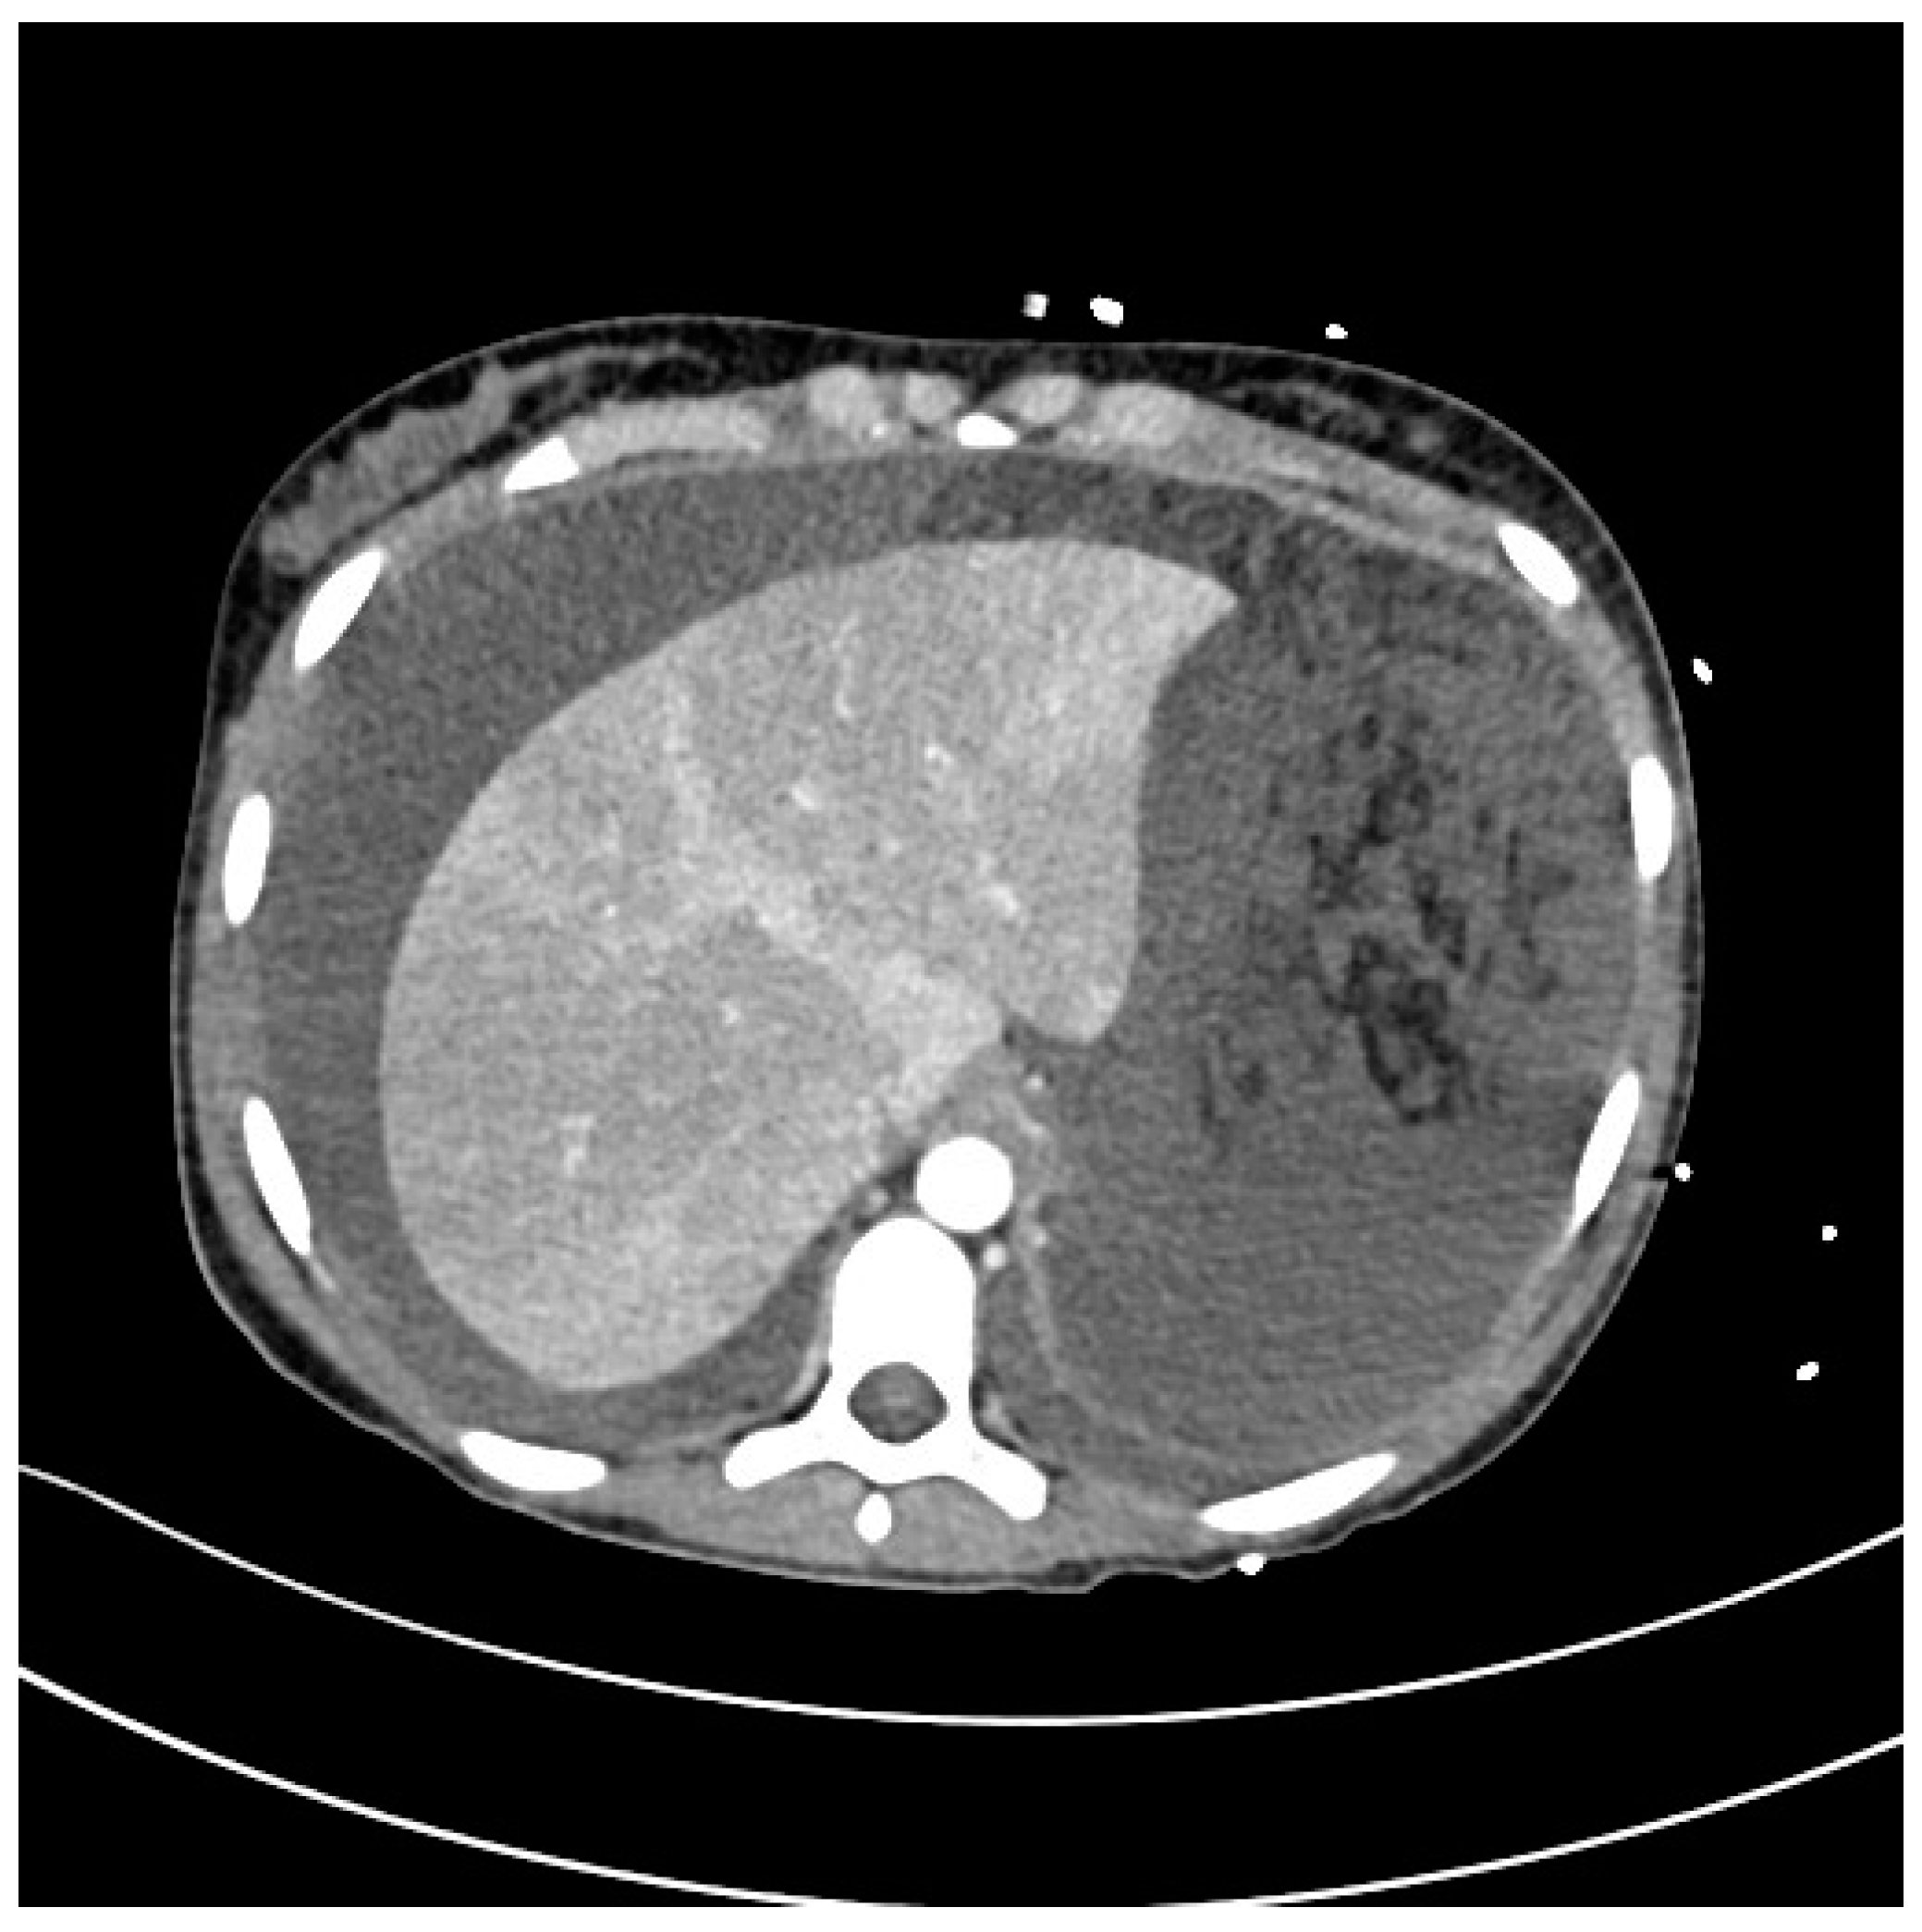

2. Case Description